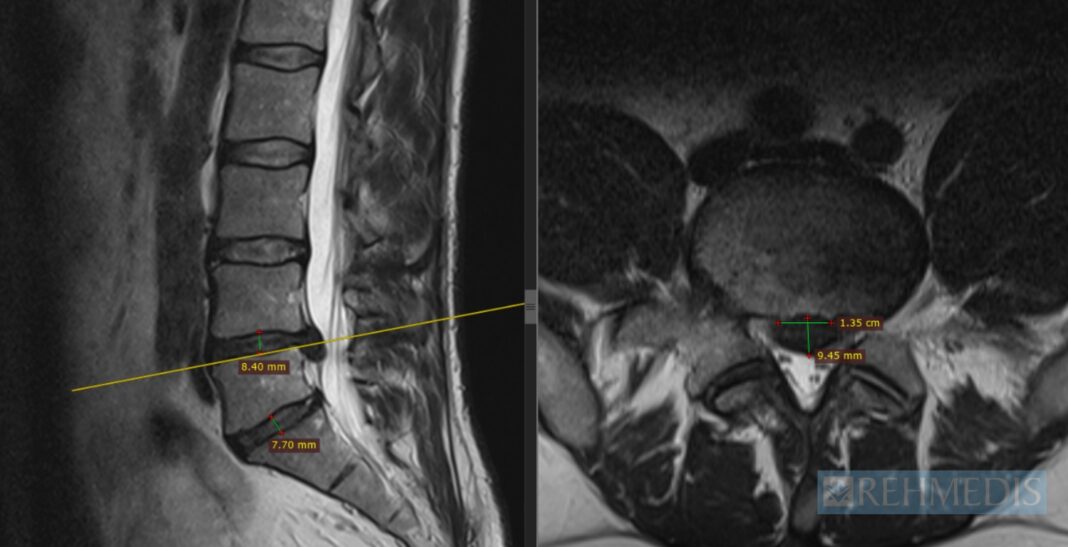

Rezonans magnetyczny, tomografia i RTG – co pokazują?

• Rezonans magnetyczny (MRI) – najdokładniejsze, pokazuje strukturę krążka, stopień przepukliny i ewentualny ucisk na nerwy.